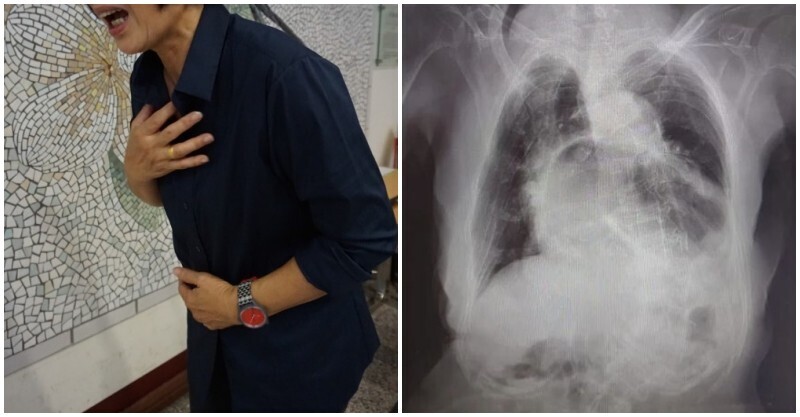

一旦上了年紀就容易會有關節疼痛的問題,據統計,台灣上百萬人有痛風困擾,而痛風是慢性腎臟病的風險因子,當痛風急性發作時不好好處例,恐會導致嚴重腎衰竭,甚至落入終身洗腎的境地。近日有研究指出,除了避開海鮮、內臟外,大家也要避開一飲品,每天攝取500cc恐讓痛風機率提升1.74倍!

痛風是一種慢性疾病,又稱作「代謝性關節炎」,由於人體在進行食物分解或是代謝排除老廢細胞時,會釋放出原本的組成成分普林,普林代謝後會形成尿酸,當血液中尿酸濃度太高,不僅會形成結晶鹽聚積在關節處,也會直接形成尿酸結石,前者會形成痛風,後者則會早成泌尿系統阻塞、影響排尿,嚴重恐造成腎積水及腎功能衰竭。

關於痛風發作的因素,很多人以為避開內臟、海鮮及過多紅肉等高普林食物,就能高枕無憂,但據美國醫學會期刊研究指出,每天攝取500cc含糖飲料,將會提高罹患高尿酸血症的機率至1.74倍,也就是說,高果糖、玉米糖漿的食物,及飲料、酒精等食品,都會造成體內尿酸累積增加,想要真正遠離痛風,一定要減低攝取高風險食物的頻率!